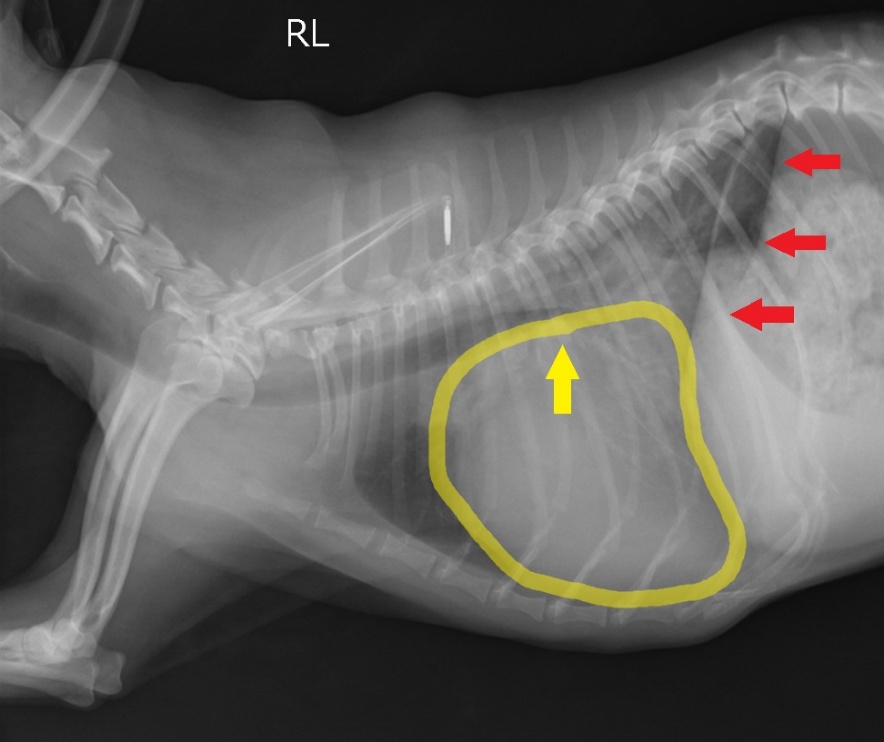

逆流によって心臓内で血液が渋滞し、初期では運動不耐性が認められます。進行すると渋滞した血液によって心臓が大きくなり、気管を圧迫して咳が出やすくなります。さらに進行すると、血液が肺から心臓に進めなくなり、肺の中に血液があふれて溺れたような状態に陥ります。これを心原性肺水腫と呼び、命にかかわります。

ステージB2:僧帽弁逆流があり、心拡大がみられる

ステージC:現在または、過去にうっ血性心不全を発症している